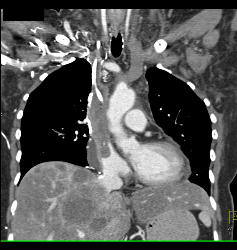

SVC Occlusion With Huge Collaterals and Thrombus Into Right Atrium